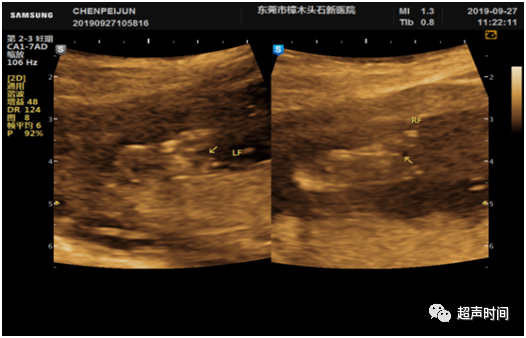

图 3 孕 13ᐩ 周。足底切面显示胎儿双足呈「V」形自足底中央部裂开,V 形尖端指向脚掌

图 4 孕 17ᐩ 周。足底切面更清楚显示胎儿双足「V」形裂开征象